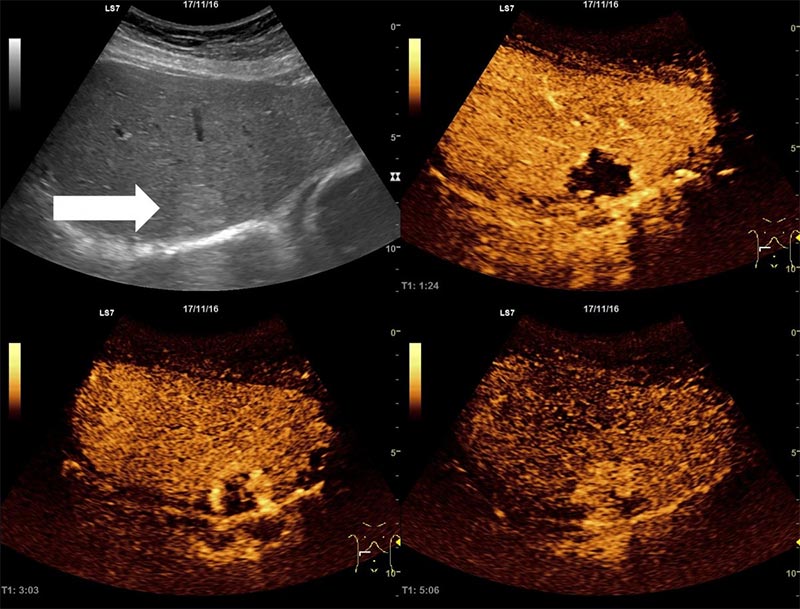

При выполнении УЗИ с контрастированием на аппаратах Mindray используется широкий спектр программного обеспечения, предназначенного как для качественной, так и для количественной оценки визуализируемых изменений. Изображения одновременно демонстрируются и записываются в двух режимах: контрастирования и серошкальном. Результаты исследования фиксируются в виде кинопетель с возможностью дальнейшей обработки и оценки количественных данных.

Ультразвуковые системы Mindray оснащены модулем для проведения контрастной эхографии UWN Plus Contrast Imaging™ с технологией сверхширокополостной нелинейной визуализации UWN+ CEUS. UWN+ CEUS позволяет регистрировать и обрабатывать нелинейные и слабые (низкоамплитудные) сигналы, что значительно повышает детализацию изображения и увеличивает время персистенции контрастного вещества при его меньшей дозировке. Технология эффективно работает как для исследования поверхностных тканей, так и для диагностики изменений глубоких структур. Дополнительно к модулю прилагается пакет программного обеспечения UWN Plus Contrast Imaging™ QA для количественного анализа результатов обследований с применением контрастных веществ.